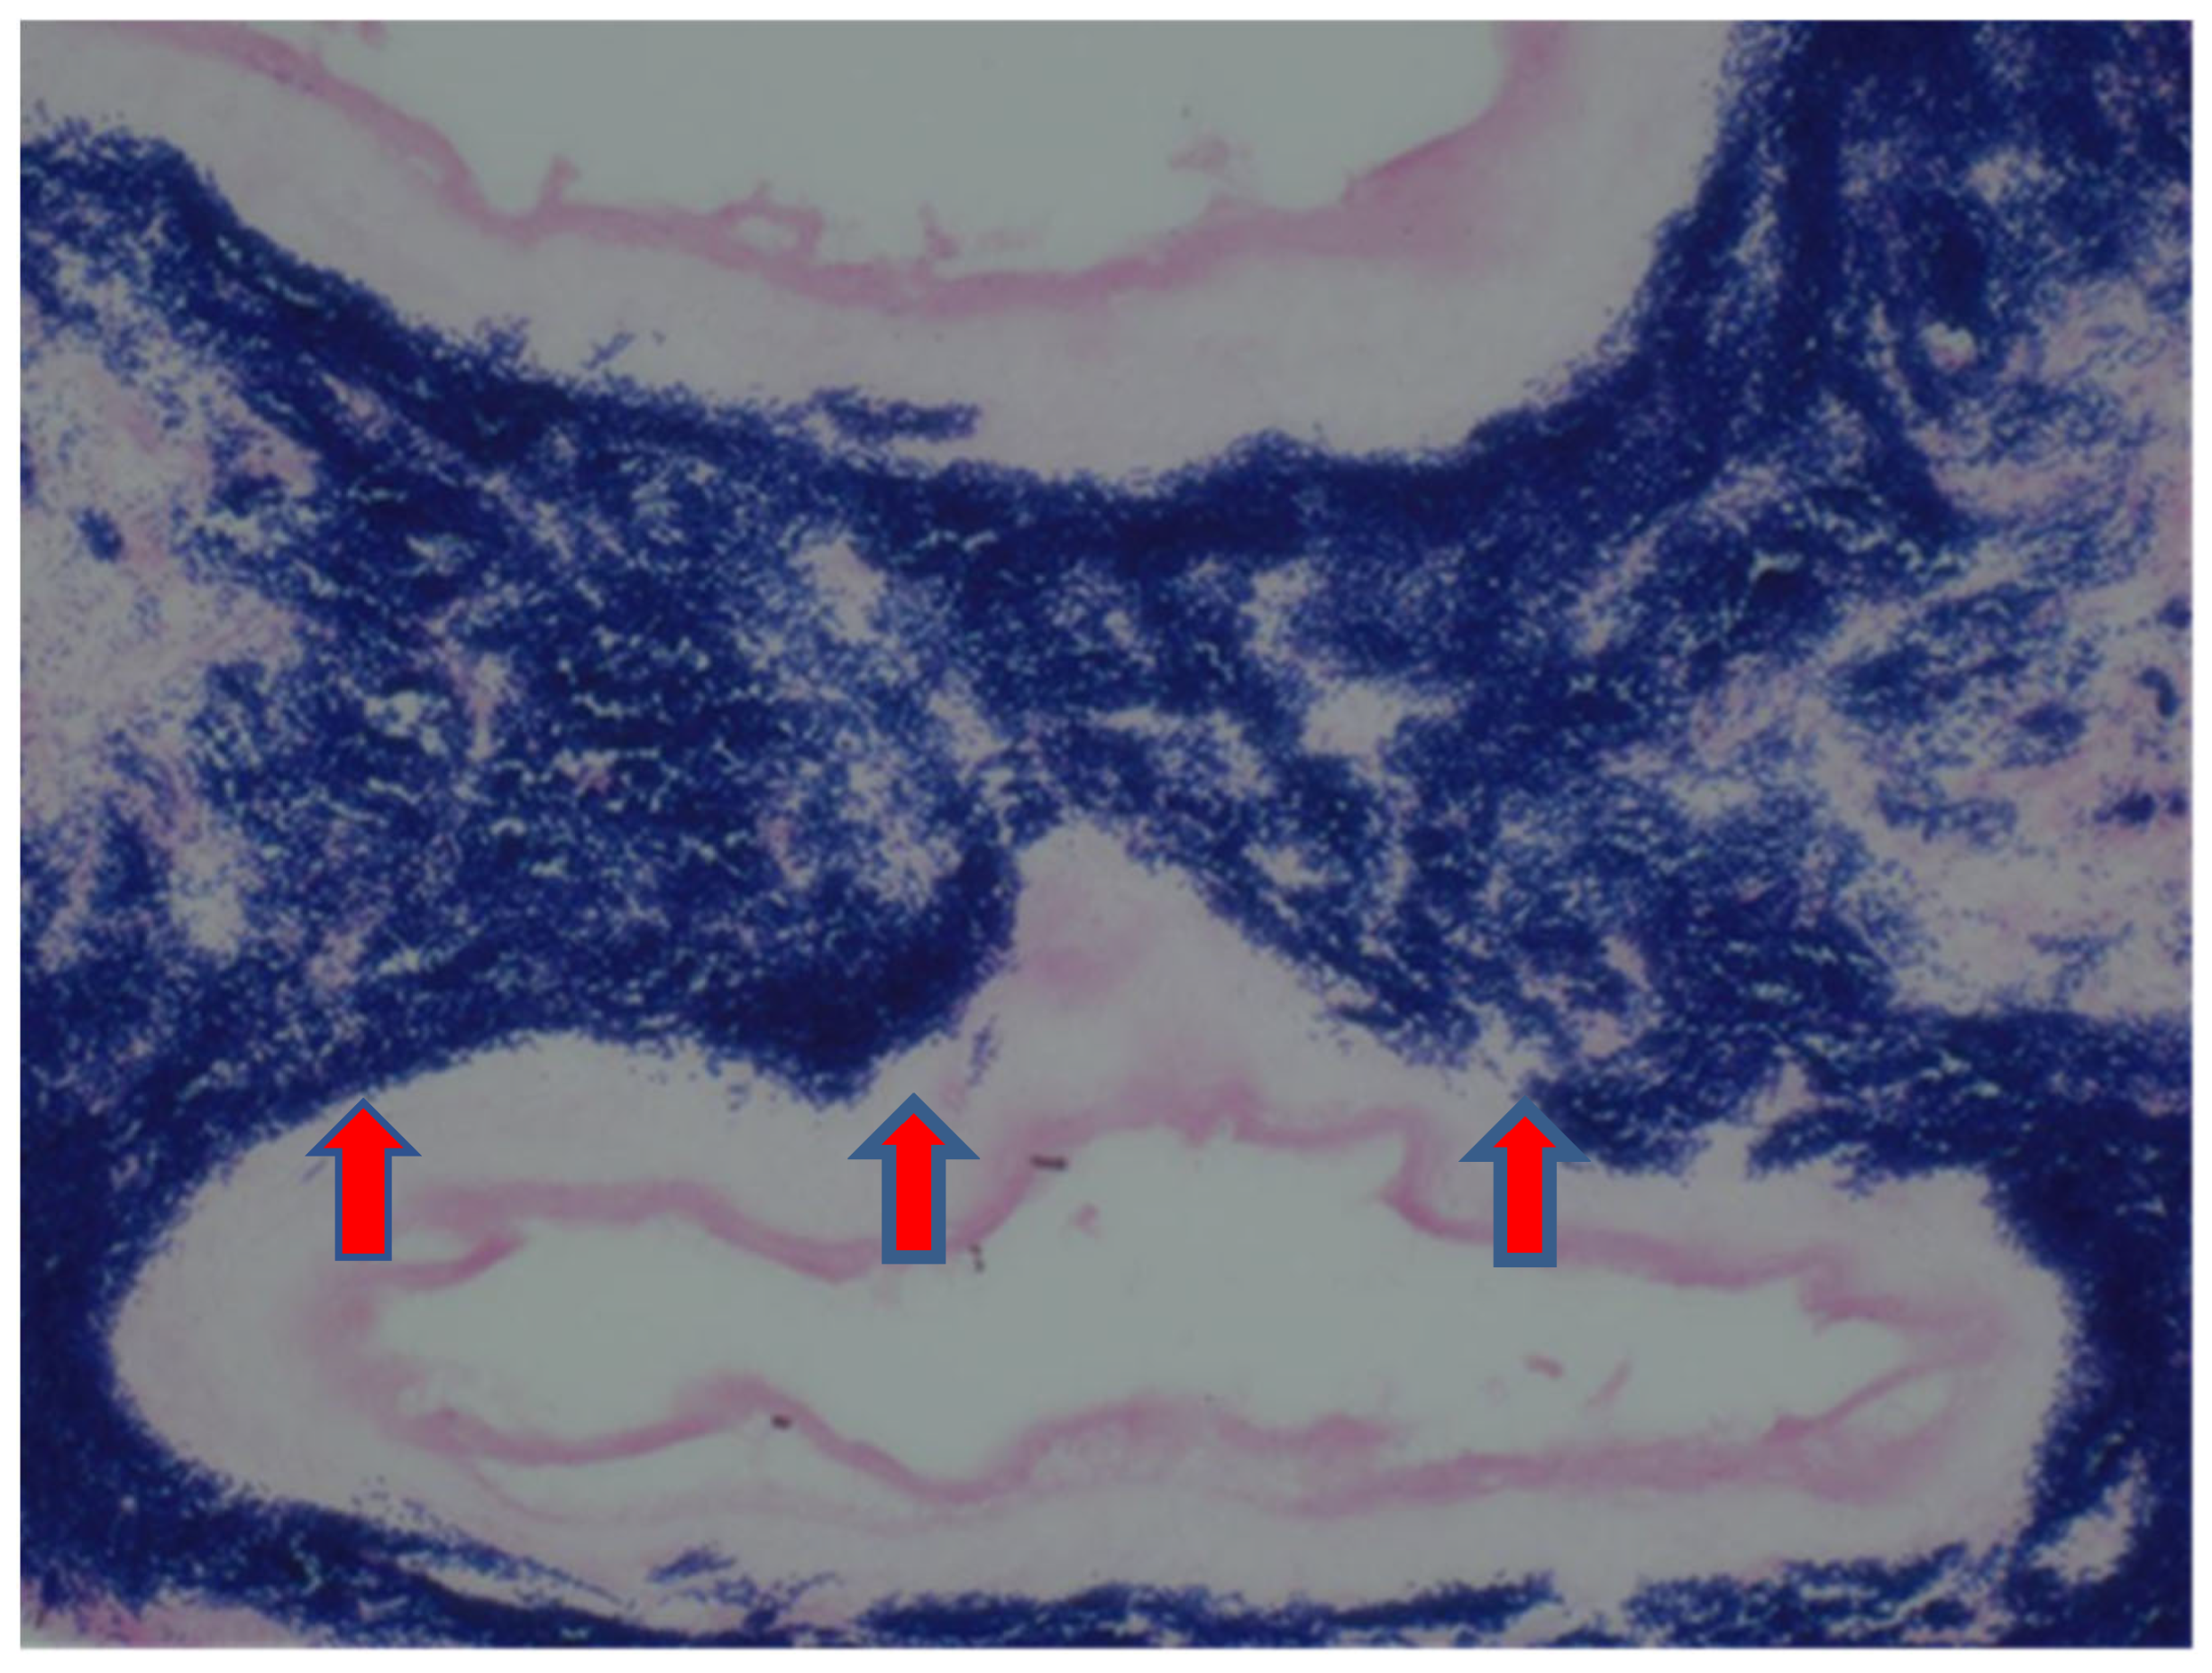

The sample received in the histopathology department was a disc of placenta and membranes with an eccentrically inserted umbilical cord. The placenta trimmed of the membranes weighed 145 mg. The membrane appeared complete and was mostly translucent but with patchy areas of opacity. Microscopy revealed patchy severe acute chorioamnionitis and prominent clusters of Gram-positive filamentous bacteria, which were noted on the surface of the membranes in routine haematoxylin and eosin (H&E) (Figure 1) as well as with Periodic Acid Schiff (PAS) staining (Figure 2). Aggregates of the Splendore–Hoeppli reaction, which are sulphur granules formed from masses of gram-positive bacteria with branching filaments, are also identifiable in Figure 2. The infective organism was revealed to be gram-positive (Figure 3). In this specific case, the microscopic examination indicated the presence of acute inflammation due to an uncommon organism—Actinomyces spp. infection. Sections of the umbilical cord revealed acute inflammation (funisitis), but no organisms were seen in the umbilical cord (Figure 4). During the follow-up visit, the mother did not demonstrate any symptom or sign of infection, her recovery was uneventful, and she remained well during the subsequent reviews.

Figure 2.

Periodic Acid Schiff (200×). Membrane containing colonies of Actinomyces organism (thick blue arrow) and multiple aggregates of Splendore–Hoeppli granules (Blue star).